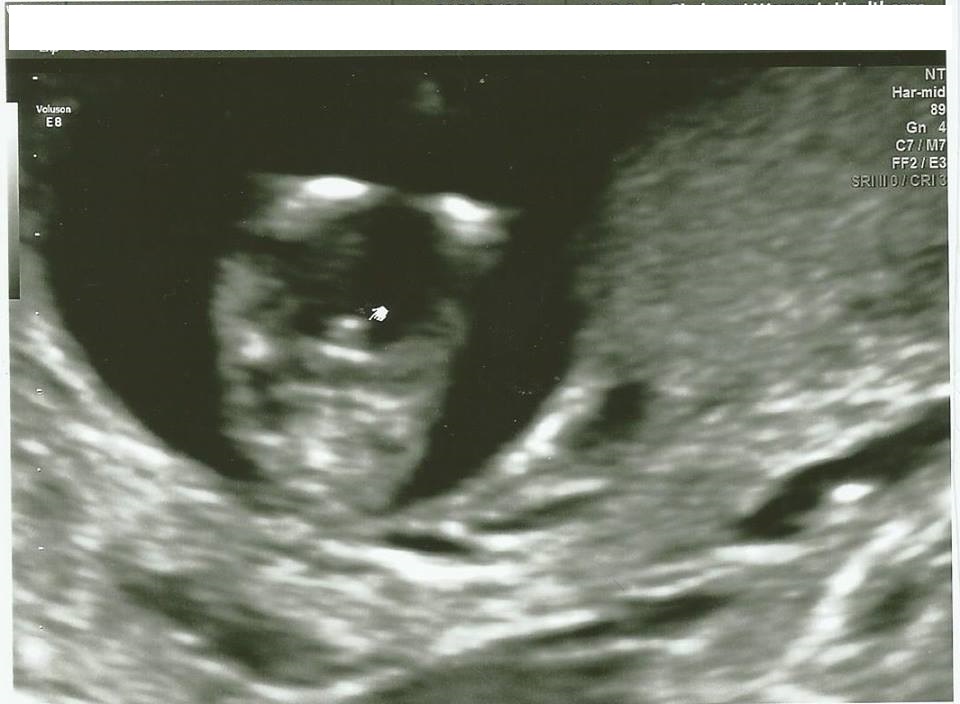

I have 4 boys, and am getting my tubes done after this baby. I had a 13 week ultrasound and the tech is pretty certain it's another boy. I can't help but to feel some sadness knowing that I will never have a little girl.... so I guess I'm here to see if anyone thinks it's too early to tell? There is obviously something between the legs, but is there any chance at all that it could be swollen girl parts?Attachment 32550

Looks very boyish to me. Congrats on your little one!

I think it is too early for a potty shot. I've seen people told wrongly on potty shots and this gestation X

Wish I could tell you otherwise, but it does appear to be a boy... As babygirlguest said it is still early for potty shots, but I would prepare to hear blue at your gender scan... Hugs Hun, and Congrats on your 5th miracle xx

Potty shots are not reliable at this stage. I agree it does look boyish but you just can't know for sure yet.